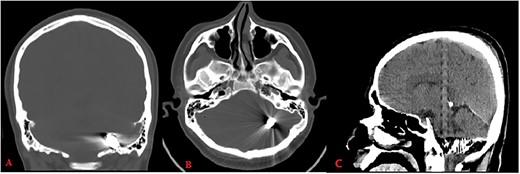

Pupils were equally reactive, and his vitals were stable. Cranial computerized tomography (CT) revealed a bone defect of 0.5 cm in the left parietal region and a metallic object located between left occipital bone and inferior side of left cerebellar hemisphere (Fig. 1).

Computed tomography (bone window: A: coronal, B: axial) reveals metallic object located between left occipital bone and inferior side of left cerebellar hemisphere; CT (brain window C: sagittal) shows hemorrhage along its trajectory.